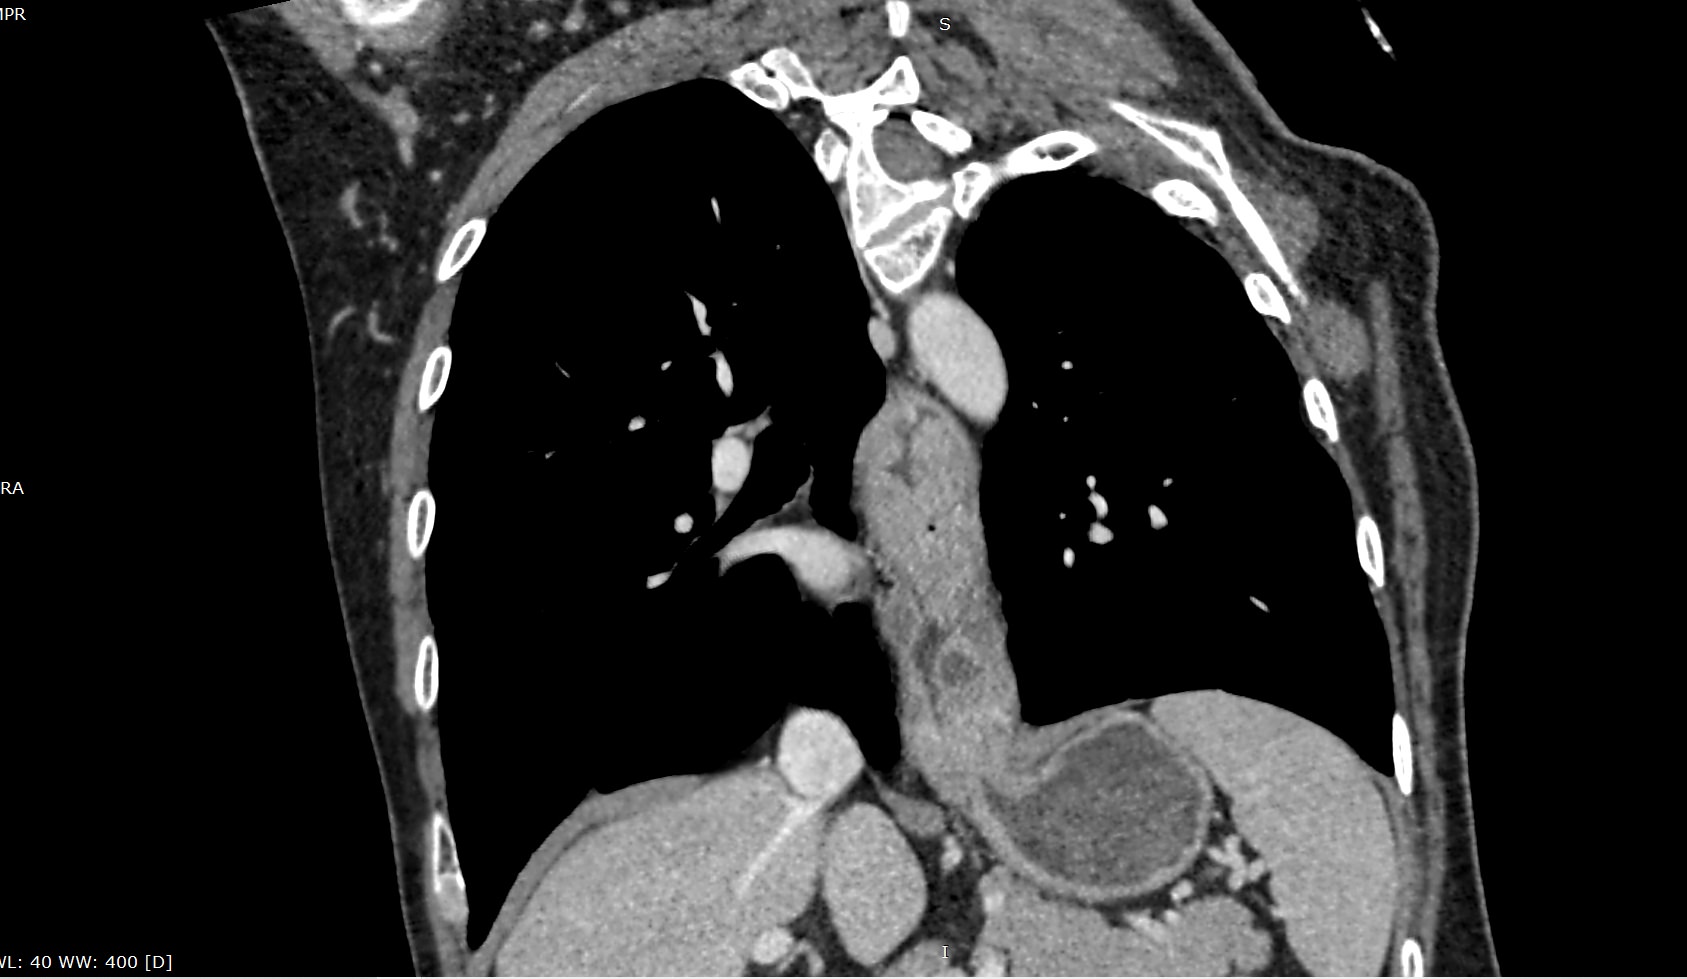

Компьютерная томография является высокоинформативным методом лучевой диагностики, который применяется для выявления заболеваний пищевода, используется при планировании оперативного лечения и для оценки успешности проведенной операции на пищеводе.

Данное исследование также позволяет оценить состояние соседних органов и тканей, включая легкие и регионарные лимфоузлы, что бывает важно для установления степени распространенности патологического процесса.

В нашей клинике исследование выполняется на новейшем 128-срезовом мультиспиральном компьютерном томографе экспертного уровня TOSHIBA AQUILION CXL. Аппарат послойно сканирует анатомическую область пищевода, выполняя срезы с минимальной толщиной от 0,5 мм, затем преобразует полученные данные в трехмерные изображения исследуемой зоны.

Томограф оснащен высокочувствительными детекторами, которые выполняют до 128 срезов анатомической области за секунды, обеспечивая превосходный уровень детализации изображений и высокое качество обследования. Кроме того увеличенное количество срезов сокращает время обследования и позволяет максимально снизить лучевую нагрузку на пациента.